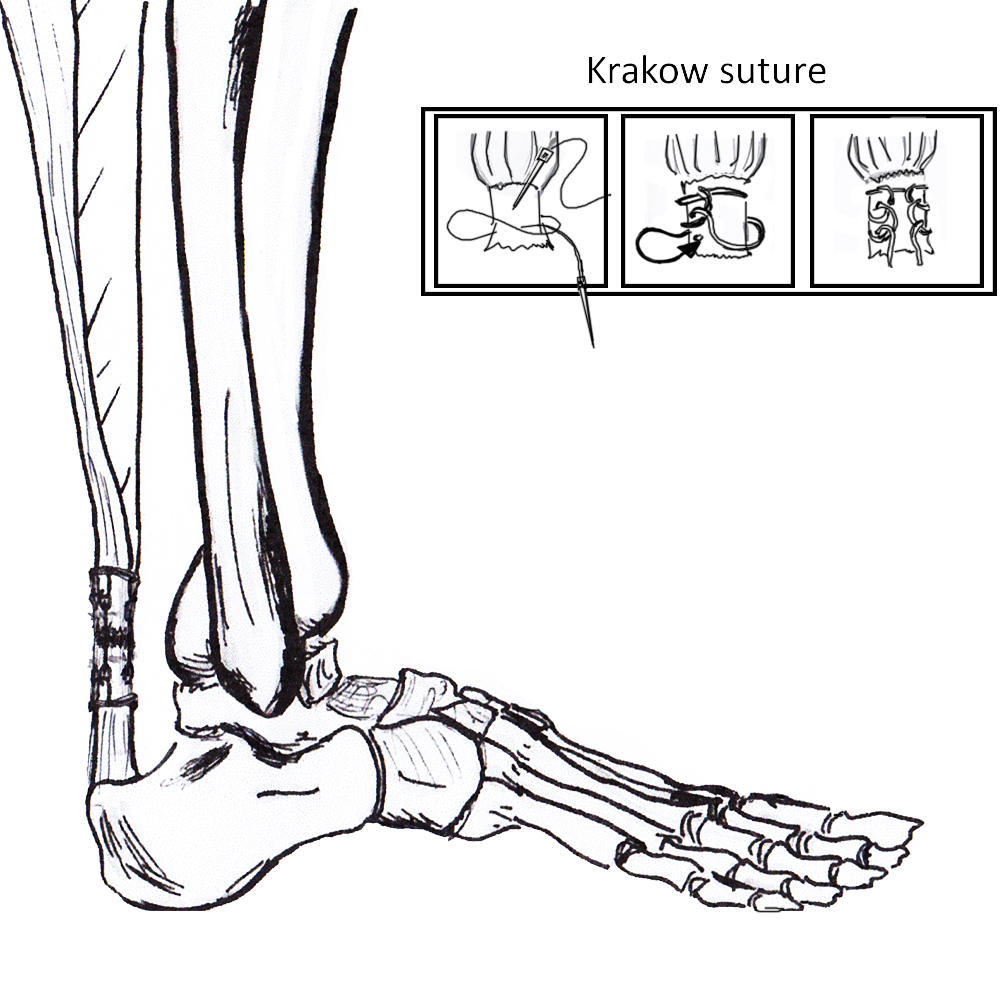

Open tendoachilles repair

Technique

Vumedi open achilles tendon repair

Prone position with tourniquet

- slightly medial incision to protect sural nerve

- full thickness skin flaps to paratenon

- identify and protect sural nerve

- divide paratenon longitudinally

- can incise paratenon in the midline anteriorly which increases tissue available for closure

- Bunnell Suture / Krackow suture x 2 with high strength suture / fibre wire

- one in proximal and one in distal tendon ends

- tie via two knots with foot fully plantar flexed

- +/- augment with circumferential 4.0 suture to minimize bunching

- careful closure of paratenon to prevent skin adhesions

- front slab in plantarflexion 2 weeks

- then standard accelerated rehabilitation

Anterior release of paratenon to allow posterior closure over achilles repair

Repair with proximal and distal Krackow high strength sutures